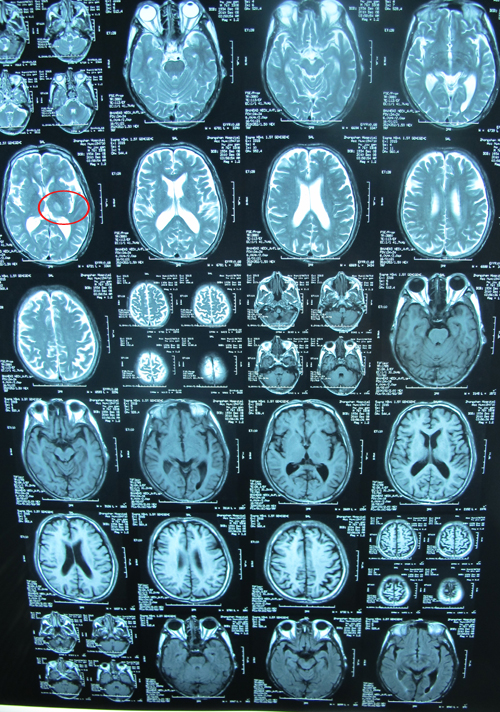

头部MRA示:左侧丘脑脑梗塞,左侧基底节区腔隙性梗塞灶,两侧额顶叶皮层下及两侧半卵圆中心多发缺血灶。脑白质病,脑萎缩。